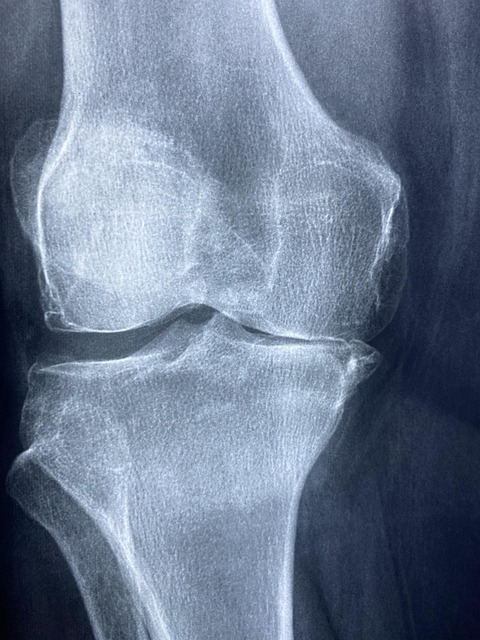

골밀도란 무엇인가? 정확한 이해가 필수!

골밀도는 간단히 말해 뼈의 밀도와 강도를 나타내는 지표입니다. 골밀도가 높다는 것은 뼈가 튼튼하고 골절 위험이 적다는 의미이죠. 반대로 골밀도가 낮으면 뼈가 약해져 작은 충격에도 쉽게 골절이 발생할 수 있습니다.

나이가 들면서 골밀도는 자연스럽게 감소하지만, 잘 관리하면 충분히 유지하거나 높일 수 있습니다. 지금부터 골밀도를 높이기 위한 핵심 방법을 알아보겠습니다.